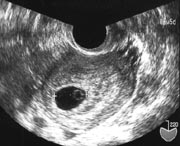

胎嚢(たいのう)によって妊娠を確認

赤ちゃんが入っている袋のことを胎嚢(たいのう)といいます。

超音波検査では、妊娠4~5週になると、子宮の中に胎嚢が黒く見えて、妊娠を確認することができます。胎嚢の中に映ったポツンと小さな白い点のようなものが胎芽です。妊娠7週まではおなかの赤ちゃんを胎児と呼ばずに、胎芽(たいが)と呼びます。

超音波検査では、胎芽の横に丸いリングが映ります。妊娠5~6週では、胎芽よりこのリングのほうが大きくはっきりと見えます。これは卵黄嚢(らんおうのう)といって、赤ちゃんのお弁当のようなもの。胎盤や臍帯(さいたい/へその緒)から栄養を受け取るようになるまでは、赤ちゃんは卵黄嚢から栄養をもらって成長します。

超音波検査には、超音波が出る器具をおなかの表面に当てる「経腹法(けいふくほう)」と、器具を腟の中に入れる「経腟法(けいちつほう)」があります。経腟法のほうが子宮の中が鮮明に見えるので、妊娠初期には経腟法による超音波検査が行われることがほとんどです。